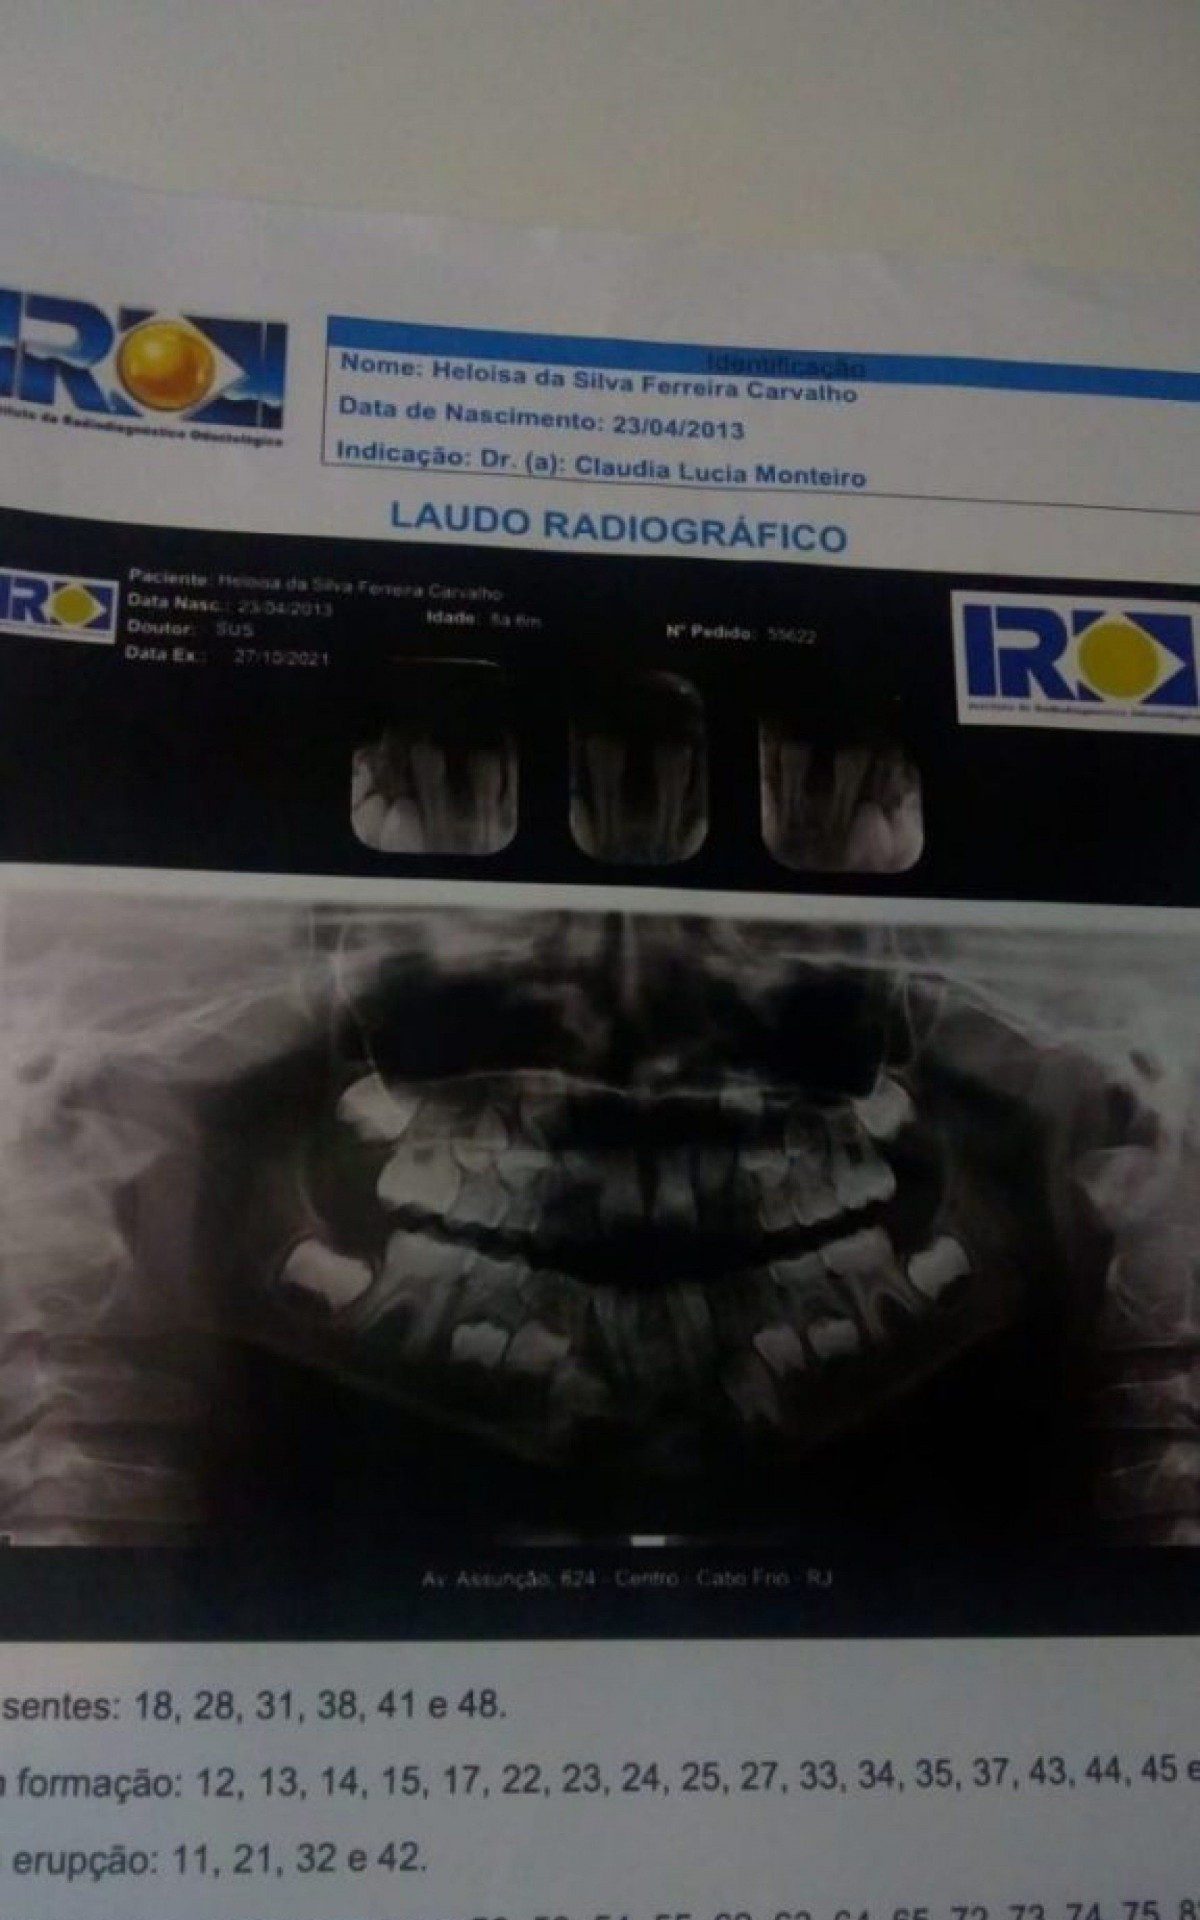

Segundo a mãe, a menina foi a consulta para extrair dois dentes de leite, diferente dos dois incisivos centrais permanentes Luiz Felipe Rodrigues (RC24h)

Segundo a mãe, a menina foi a consulta para extrair dois dentes de leite, diferente dos dois incisivos centrais permanentes do arco inferior da boca da garota arrancados na ocasião.